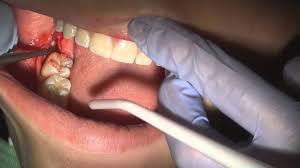

Bác sĩ vệ sinh sạch sẽ răng miệng, để không đau đớn và tạo sự thoải mái cho bệnh nhân, bác sĩ gây tê cho bệnh nhân trước khi nhổ răng.

Bác sĩ làm lung lay răng bằng cây nạy nha khoa, sau đó dùng kìm chuyên dụng nhổ răng ra khỏi xương hàm.

4. Cầm máu.

Bác sĩ thực hiện đặt kem co mạch để cầm máu cho bệnh nhân.

Sau nhổ răng, bệnh nhân cần cắn gòn cầm máu ít nhất trong 10 phút.